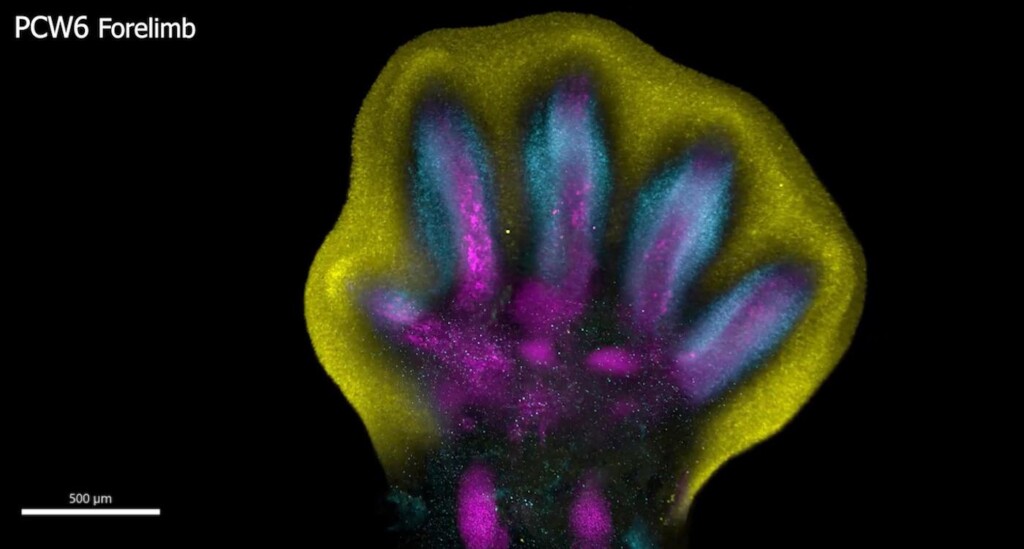

Scientists have uncovered unprecedented insights into the formation of human hands and feet and the intricate processes that govern their development.

Human fingers and toes do not grow outward; instead, they form from within a larger foundational bud, as intervening cells recede to reveal the digits beneath.

This is among many processes captured for the first time as scientists unveil a spatial cell atlas of the entire developing human limb.

Special staining of the tissue revealed clearly how cell populations differentially arrange themselves into patterns of the forming digits.

Limbs are known to initially emerge as undifferentiated cell pouches on the sides of the body, without a specific shape or function. But after 8 weeks of development, they are well differentiated, anatomically complex and immediately recognizable as limbs, complete with fingers and toes.

In this new study, scientists from the Wellcome Sanger Institute, Sun Yat-sen University, and their collaborators analyzed tissues between 5 and 9 weeks of development. This allowed them to trace specific gene expression programs, activated at certain times and in specific areas, which shape the forming limbs.